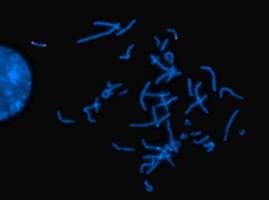

Biowissenschaften - Gesundheit - 23.07.2020

Brüche und Umlagerungen im Erbgut können zu schweren Erkrankungen führen, selbst wenn die Gene dabei intakt bleiben. Eine zuverlässige und genaue Diagnose solcher Defekte verspricht Hi-C, eine Methode zur Analyse der dreidimensionalen Struktur von Chromosomen, die derzeit in der Klinik noch nicht genutzt wird.